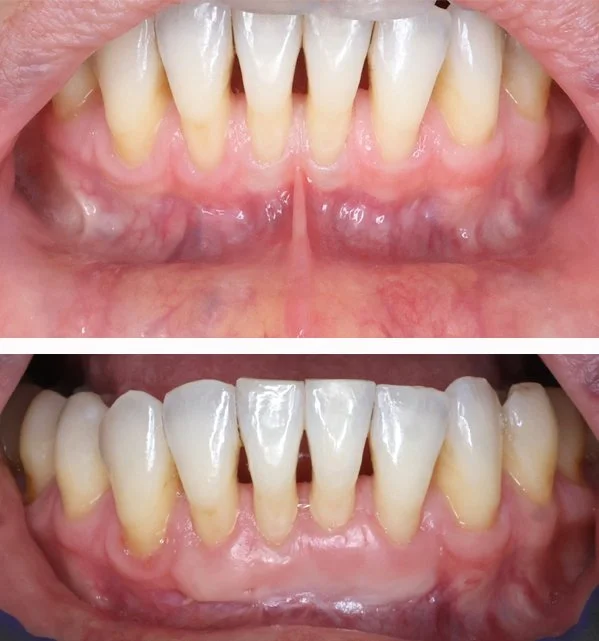

Soft Tissue Graft

We treat gum recession to enhance aesthetics, strengthen gum tissue, and provide better long-term support for teeth and dental implants.

Free Gingival Graft

Free Gingival Graft (premolars)